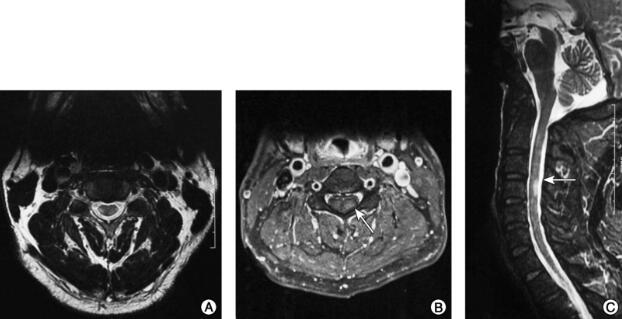

①头颅MRI(2015-12-30)(图1):双侧额叶深面、侧脑室旁、半卵圆中心白质内多发点状稍长T1稍长T2信号,FLAIR高信号,部分病变DWI高信号,增强扫描左侧基底节区、侧脑室旁见数个斑点状强化。②头颅MRI(2016-9-14)(图2):双侧基底节、侧脑室旁、半卵圆中心见多发点片状长T1长T2信号,部分与脑室垂直,DWI呈稍高信号;增强扫描未见异常强化;MRS示较大病灶处Cho峰轻度升高、NAA峰轻度下降,未见高灌注。③头颅MRI(2017-6-1):双侧基底节、侧脑室旁、半卵圆中心见多发点片状长T1长T2信号,部分与脑室垂直,DWI低信号,与2016年9月14日片比较未发现新发病灶。④颈胸椎MRI(2015-12-30)(图3):C3~C5脊髓稍长T1稍长T2信号,增强扫描呈环形强化。

图3 颈胸椎MRI(2015-12-30)检查结果

注:A~C.C3~C5脊髓稍长T1稍长T2信号,增强扫描呈环形强化。